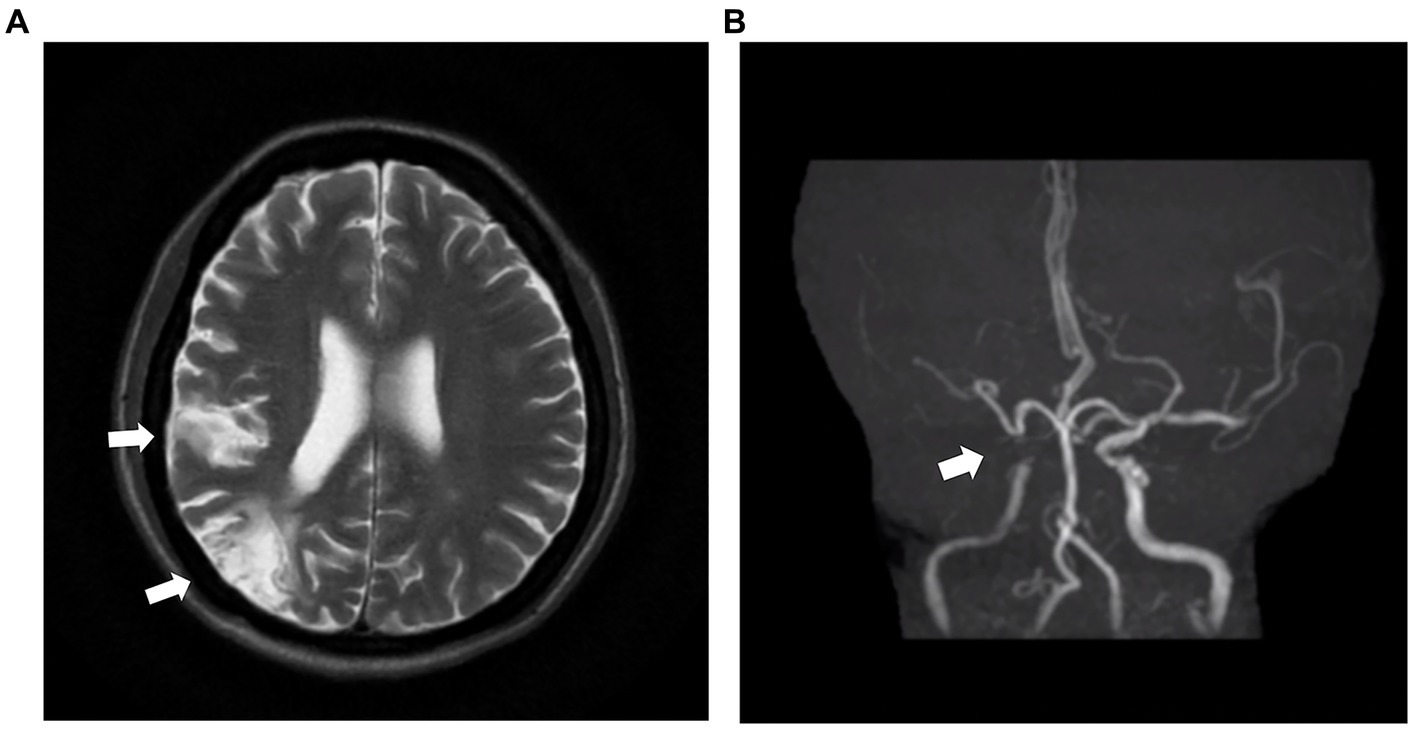

Laboratory examination showed satisfactory blood glucose control, normal hemoglobin, and a lack of elevation of inflammatory markers, such as erythrocyte sedimentation rate and C-reactive protein; however, elevated platelet levels (593 × 109/L) were noted. Serum calcium (2.14 mmol/L), serum phosphorus (1.50 mmol/L), and uric acid levels (357 μmol/L) were normal. The liver, kidney function, and thyroid function were normal, while the levels of estradiol (E2 114.73 pmol/L), luteinizing hormone (LH 0.98 mIU/mL; reference value, 10.87–58.64 mIU/mL), and follicle-stimulating hormone (FSH 1.46 mIU/mL; reference value, 16.74–113.59 mIU/mL) were low. Serum cortisol was slightly raised (8 am 511.70 nmol/L; 0 am 234.50 nmol/L) along with elevated adrenocorticotropic hormone (ACTH 124.30 pg/mL; reference value, 6.0–48.0 pg/mL). Immunoglobulin levels were normal. Magnetic resonance imaging of the head revealed two infarctions in the right parietal lobe and temporo-occipital junction due to the occlusion of the right internal carotid artery and right middle cerebral artery (Figure 2). Following a detailed inquiry into the medical history, we discovered that transient coughing occurred upon drinking water. Incontinence was present without hemiplegia, and the patient was inattentive. Neuroelectrophysiological examination showed that the conduction velocity of the motor and sensory nerves of the limbs was reduced, the latency of the F wave of the upper limbs was prolonged, and the F wave of the left lower limbs was not elicited, suggesting severe involvement of multiple peripheral sensory and motor nerves with axonal and demyelinating damage in the limbs. Neuropathy was more severe in the lower limbs than in the upper limbs. Subsequently, a lumbar puncture examination was performed. There was no evidence of protein–cell separation in the cerebrospinal fluid. However, considering the patient’s medical history, symptoms, signs, and neuroelectrophysiological examination results, the possibility of CIDP was suspected. Prednisone was administered with the permission of the patient and her husband. After 1 month of medication, the patient’s symptoms of limb weakness improved, and the upper and lower limb muscle strengths returned to approximately level 5. However, there was no improvement in ankle edema. Imaging findings, including a small amount of pleural and pericardial effusion, mild pulmonary hypertension, plump liver and spleen, and vertebral osteosclerosis (Figure 3), provided clues for investigating the underlying disease. Blood light chain λ was 987.00 mg/dL (reference value, 280–665 mg/dL). An abnormal band, accounting for approximately 7.0%, was observed in the γ region during serum protein electrophoresis. Type IgG-λ M protein was determined by serum immunofixation electrophoresis. Bone marrow puncture and biopsy revealed active proliferation of the bone marrow, a normal proportion of plasma cells, and a few scattered plasma cells in the bone marrow. Immunohistochemical analysis revealed the absence of significant monoclonal cells. Additionally, the level of vascular endothelial growth factor (VEGF) was substantially elevated, with a value of 1145.72 pg/mL (normal range 0–142 pg/mL).

Figure 2

MRI and MRA images of the head of the patient. (A) The head MRI shows two infarctions at the right parietal lobe and temporo-occipital junction (white arrow). (B) The right internal carotid artery and right middle cerebral artery demonstrate severe stenosis and are almost occluded (white arrow). MRI: magnetic resonance imaging. MRA: magnetic resonance angiography.

The patient’s blood glucose and blood pressure were under control, with no history of smoking, drinking, or genetic disease. However, at the age of 54 years, the patient exhibited serious occlusion of the cerebral and lower extremity arteries. VEGF increases vascular permeability and promotes vascular endothelial cell proliferation and neovascularization, leading to systemic vascular stenosis/occlusion (22). A study by Sugiyama demonstrated that approximately half of patients with POEMS syndrome exhibited major cerebral artery stenosis/occlusion on initial MRA/CTA (23). Multiple vascular involvement was observed in approximately one-third of all patients with POEMS syndrome. Severe peripheral vascular and nervous system diseases can result in the development of refractory foot ulcers.